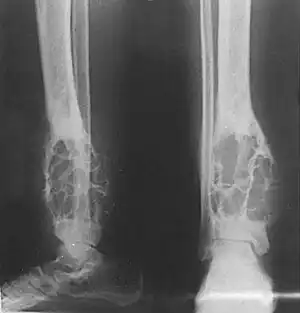

X-ray (side and front views) showing an adamantinoma in the large bone of lower leg, near the ankle. | |

X-rays of the affected area show a well defined tumor in bone, with multiple lobules giving a "soap bubble" appearance.[2] MRI can provide a more useful guide to its severity.[2]

X-rays of the affected area show a well defined tumor at the edge of the bone, with multiple lobules giving a "soap bubble" appearance.[2] MRI can provide a more useful guide to its severity.[2]